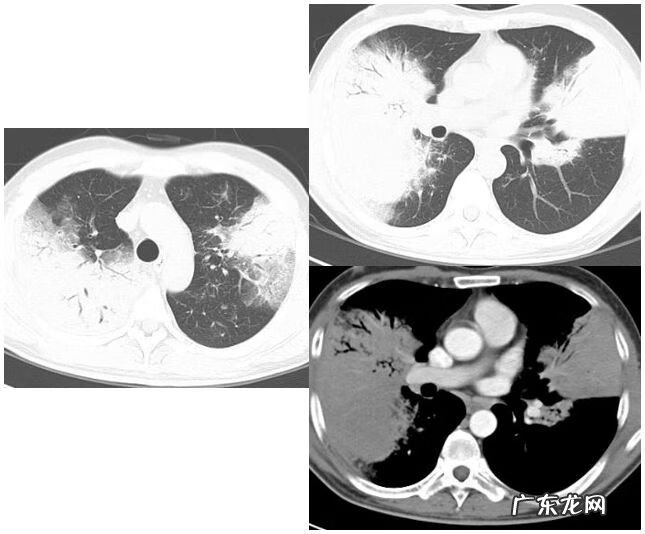

大叶性实变型也就是双下肺实变影,伴有支气管充气征 。这是一位52岁的女性,咳嗽胸闷3个月,咳白色粘痰,由于抗细菌及真菌效果不佳,当时考虑肿瘤或者OP,但是仔细看,它的叶间裂后移,肺的体积是缩小的,支气管可见不规则轻度扩张,这也提示病变是收缩的概念,并不是像肿瘤一样的膨胀性生长的改变 。肺穿刺活检证实OP,激素治疗3月,肺内病变基本吸收仅残留少许磨玻璃密度影 。

激素治疗3月后

这是一位71岁的女性,咳嗽咳痰,发热20余天,最高体温39度,抗炎效果不佳 。右肺的大片状实变影,叶间裂积液,还有淋巴结增大,增强后病灶密度不均匀,明显强化,30hu以上 。仔细观察细支气管,末梢有一种扩张、牵拉的改变,血管走行未见明显异常 。最开始诊断为大叶性肺炎,没有想到OP,因为影像学表现很相似,有实变磨玻璃影、小叶间隔增厚,胸腔 积液等改变,患者临床表现也类似感染,经肺穿刺活检证实为OP 。激素治疗2年,肺内病变基本吸收仅残留少许磨玻璃密度影,但是左肺又新出现磨玻璃密度影,这就是病情反复的特点 。

激素治疗2年